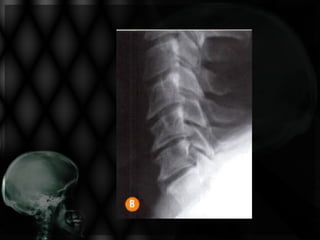

• Paciente com 67 anos apresenta cervicalgia persistente

com irradiação para face lateral de MS direito, associada

à hipotrofia do membro e hipertonia da musculatura

cervical.

• Solicitou-se RX Cervical!

Não evidencia-se neste RX de perfil:

Anterolistese C5  C6

Retificação da lordose fisiológica

Osteofitose anterior generalizada

Redução do espaço discal C5 C6 e

C6 C7